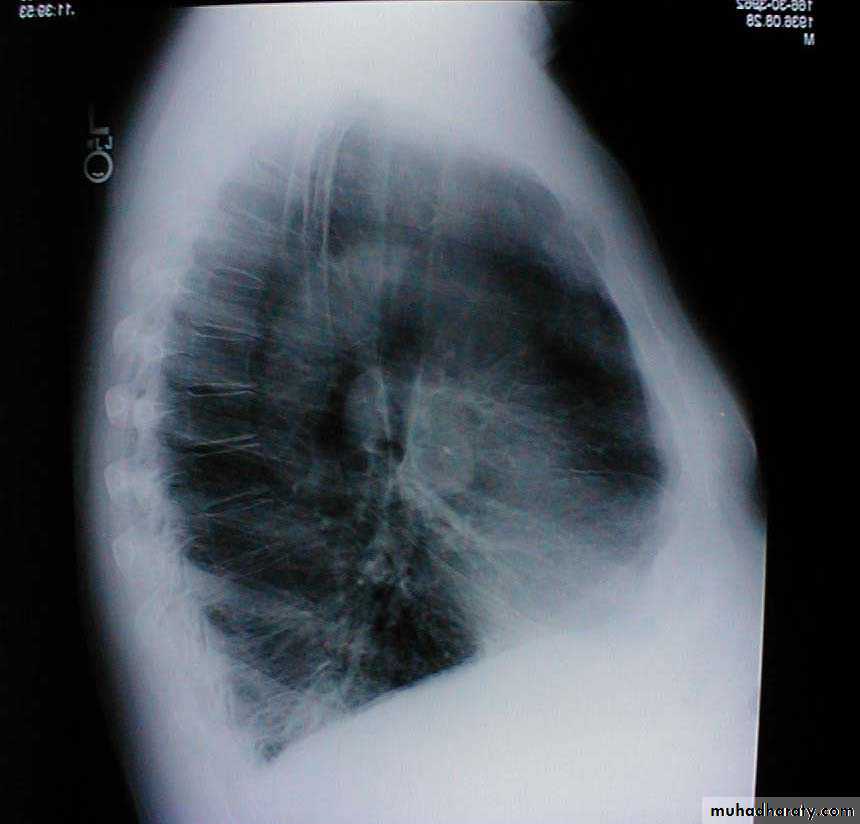

Barrel chest: Associated with emphysema and lung hyperinflation. Accompanying xray also demonstrates increased anterior-posterior diameter as well as diaphragmatic flattening.